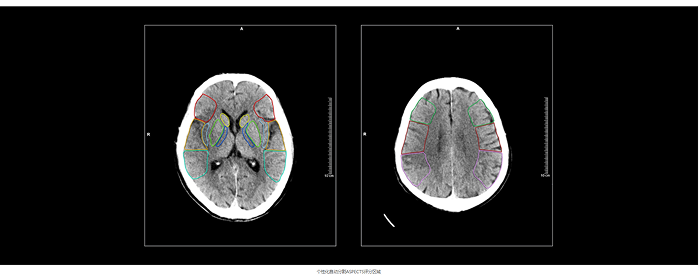

搭载该算法的联影智能CT脑缺血智能分析系统可精确分割并定位ASPECTS评分区域,自动提供左、右脑ASPECTS评分并标记早期缺血改变区域,提供ASPECTS评分预后参考指南及随访分析,帮助医生提高阅片准确度和一致性,将评分时间从几分钟缩短至几秒钟,把握治疗黄金时机。